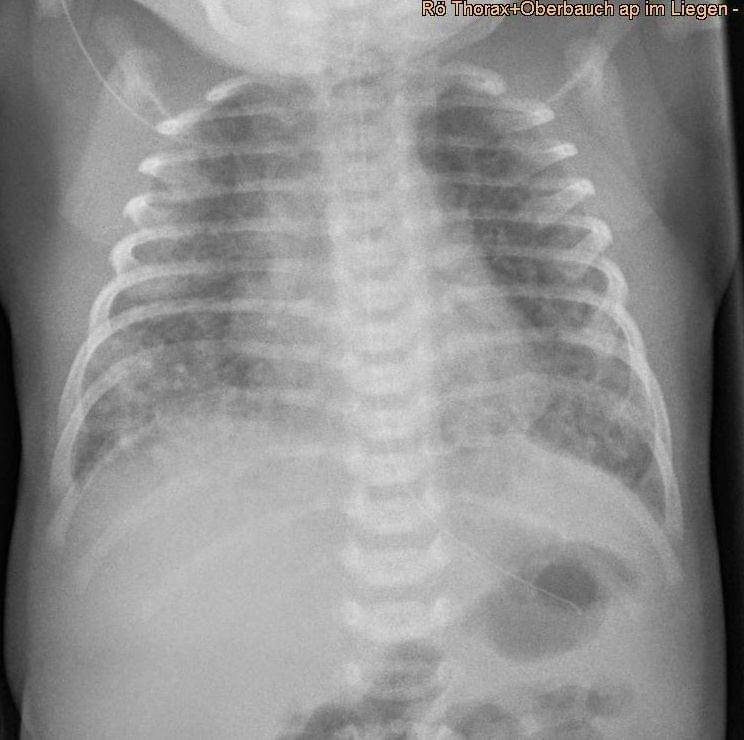

Rontgen dada mungkin menunjukkan area yang tidak rata atau bergaris-garis di paru-paru bayi.